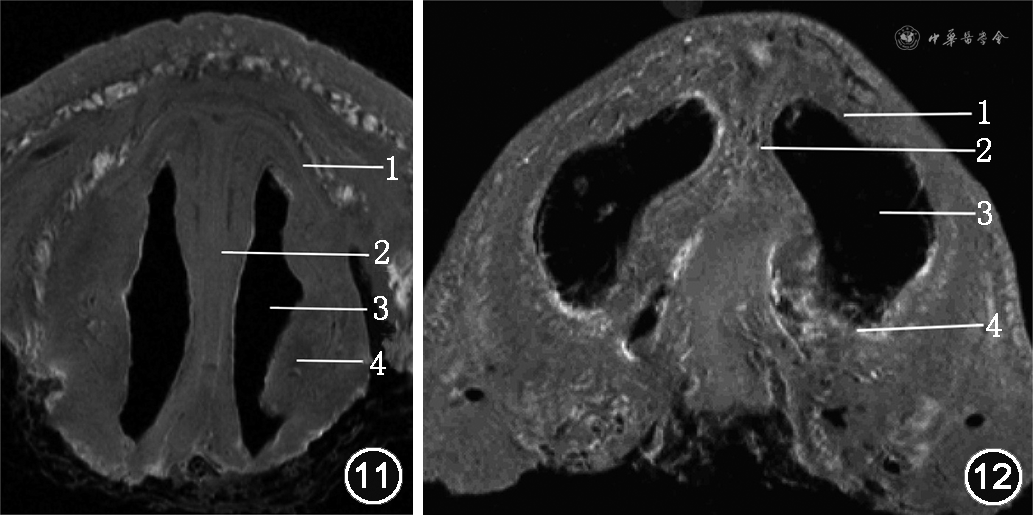

1. 内鼻阀:内界为鼻中隔尾侧端,外上界为ULCs尾侧端,外下界为下鼻甲前端,下界为鼻底(图11)。内鼻阀是鼻阻力的主要来源。鼻中隔高位或前端偏曲、鼻中隔前部增厚、ULCs内移或下陷、下鼻甲肥大均是引起内鼻阀动态或静态狭窄最常见的原因,会使鼻阻力增加,引起鼻塞。

2. 外鼻阀:内界为GACs内侧脚、鼻小柱,上界、外界为鼻翼缘,主要由GACs外侧脚和皮肤软组织构成,下界为鼻前庭(图12)。外鼻阀是鼻阻力的另一来源。鼻尖低垂、鼻前庭瘢痕、狭窄均会导致外鼻阀狭窄,引起鼻阻塞;此外,鼻部肌肉力量减弱、GACs外侧脚薄弱、硬度不够、位置异常等会导致吸气时鼻翼塌陷、外鼻阀狭窄,引起鼻阻塞。